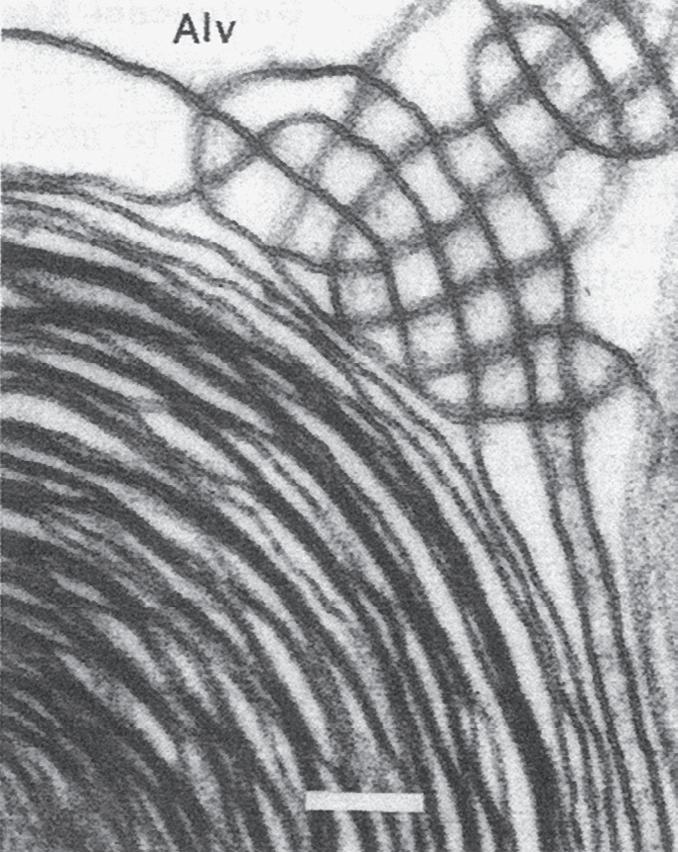

Fig. 1.5 Transmission electron micrograph of a pulmonary capillary in cross section. Alveoli (Alv) are on either side of the capillary that is shown with a red blood cell (RBC). The diffusion pathway for oxygen and carbon dioxide (arrow) consists of the areas numbered 2, 3, and 4, which are the alveolar–capillary barrier, plasma, and erythrocyte, respectively. BM, basement membrane; C, capillary; EN, capillary endothelial cell (note its large nucleus); EP, alveolar epithelial cell; FB, fibroblast process; IN, interstitial space. (Reproduced with permission from Weibel ER. Morphometric estimation of pulmonary diffusion capacity, I. Model & method. Respir Physiol. 1970;11:54–75.)

The barrier between the gas in the alveoli and the red blood cells is only 1 to 2 μm in thickness and consists of type I alveolar epithelial cells, capillary endothelial cells, and their respective basement membranes (Fig. 1.5). O2 diffuses across this barrier into plasma and red blood cells, whereas the reverse occurs for CO2 (see Chapter 8). Red blood cells pass through the pulmonary network in less than 1 second, which is sufficient time for CO2 and O2 gas exchange to occur.

In some regions of the alveolar wall there is nothing between the airway epithelial cells and the capillary endothelial cells other than their fused basement membranes. In other regions there is a space between the epithelial and endothelial cells called the interstitial space or interstitium (see Fig. 1.5). The interstitium is composed of collagen, elastin, proteoglycans, a variety of macromolecules involved with cell–cell and cell–matrix interactions, some nerve endings, and some fibroblast-like cells. The alveolar septum creates a fiber scaffold through which pulmonary capillaries are threaded and is supported by the basement membrane. There are also small numbers of lymphocytes that have migrated out of the circulation in the interstitium and capillary endothelial cells. The basement membrane is capable of withstanding high transmural pressures and sometimes is the only remaining separation between blood and gas.